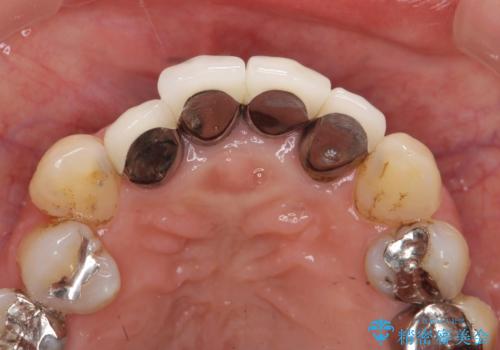

前歯の黒ずみ セラミッククラウン改善

- 20年前に治療した前歯の劣化・審美障害の改善を求めて来院されました。

クラウンを除去し審美的なジルコニアクラウンによる補綴の再作製計画を立案します。

クラウンの適合について

クラウンと支台の適合が悪いと内部に汚れがたまり虫歯の再発・審美性の障害・口臭の発生リスク方あまります。